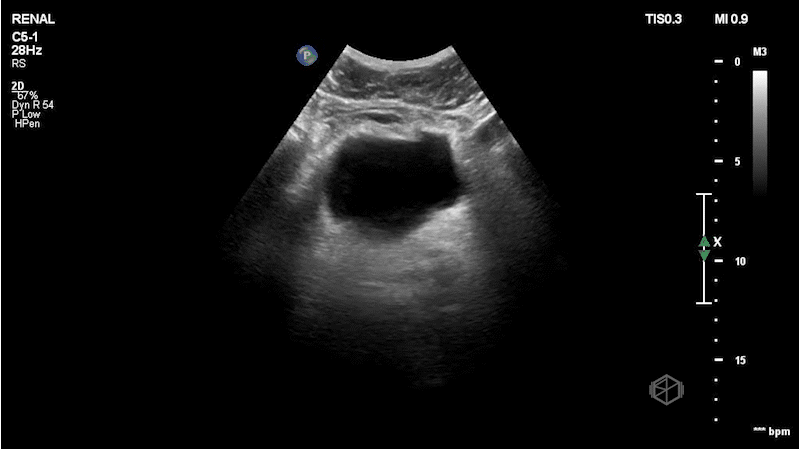

This was the patient’s FAST examination:

This FAST examination is clearly positive, with large amounts of complex fluid near the liver tip in the first clip. In the 2nd and 3rd clip, note the absence of the normal contour of the spleen. There is also free fluid at the tip of the spleen.

The patient had a CT that demonstrated AAST spleen grade grade 5 splenic injury based on active bleeding with hemoperitoneum and splenic laceration and left fourth through eighth rib fractures.

Diagnosis: Grade 5 splenic laceration with hemoperitoneum and active extravasation

• Swirling internal echoes in this scan likely indicate active hemorrhage.

• Normally the spleen on ultrasound is smooth and homogeneous. Evaluating the heterogeneity of the spleen can indicate splenic injury (36601219, 23175018).